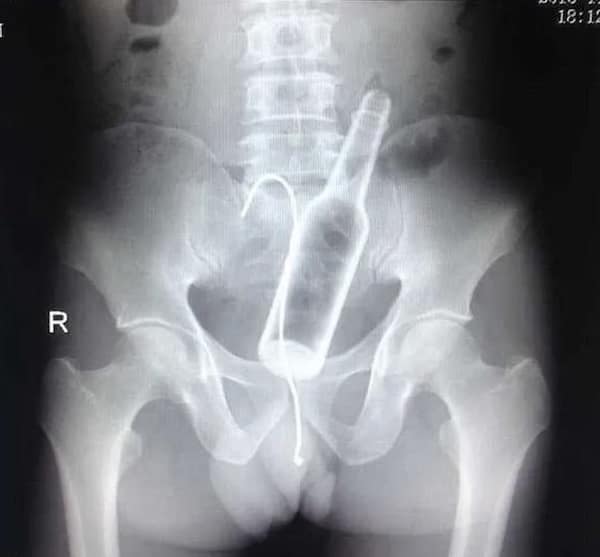

Weird xray photos

I used to think that nothing could surprise me anymore—until I stumbled upon some weird x-ray photos that made me reconsider my stance on human ingenuity (or lack thereof). Apparently, some people have a knack for getting objects lodged where they absolutely shouldn’t be. If you’ve ever wondered how not to use everyday items, these images might provide some unintended guidance.

This collection showcases 31 bizarre x-ray images that defy logic and anatomy textbooks alike. Each photo reveals unexpected objects making cameo appearances inside the human body, turning medical imaging into a gallery of the absurd. From common household items inexplicably found in unusual places to anomalies that would leave even seasoned doctors scratching their heads, these images offer a perplexing glimpse into the more “creative” side of medical emergencies. They highlight the intersection of curiosity, misadventure, and perhaps a dash of poor decision-making, all captured through the lens of radiology.